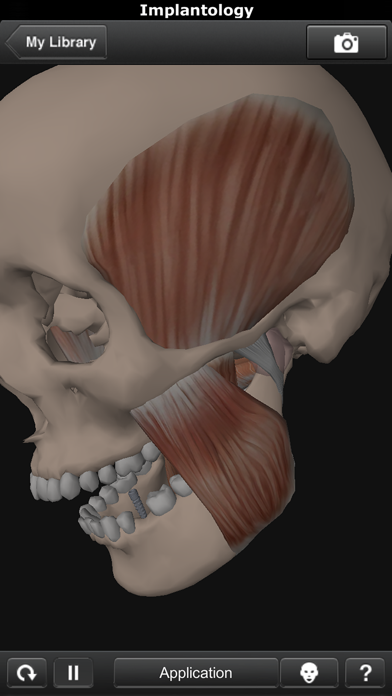

Скриншоты